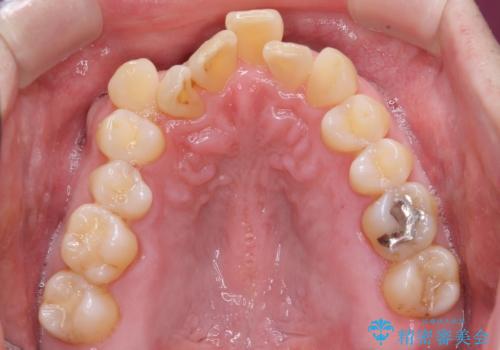

矯正治療後、右下のインレーブリッジおよび左下の銀歯のやりかえを行なっています。

右上の八重歯は、右上の奥歯を矯正用ミニスクリューを用いて遠心移動を行い解消しました。

下の前歯はIPR(エナメル質を薄く削り歯を小さくする処置)を行なっています。